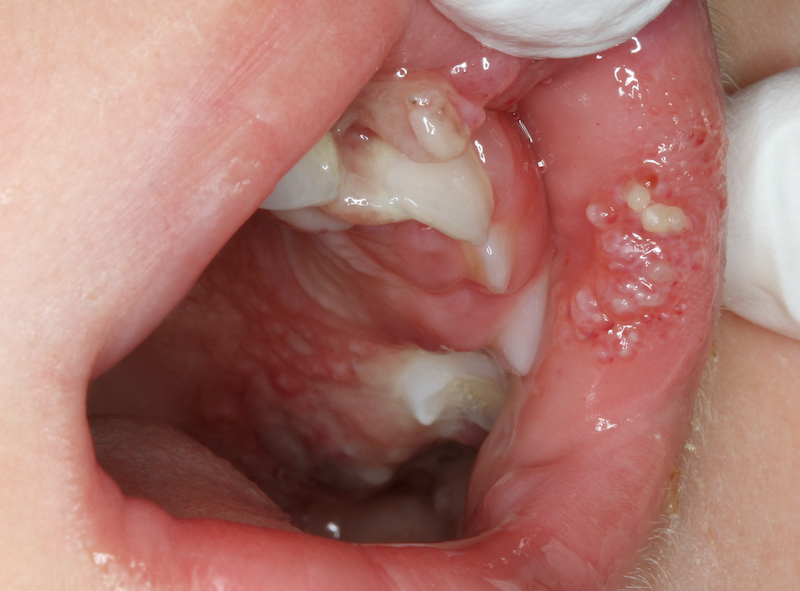

© Prof. A. Rahman

Die sichere Durchführung zahnärztlicher Narkosen bei Kindern erfordert eine enge interdisziplinäre Zusammenarbeit, individuelle Risikobewertung, angepasste Anästhesie- und Überwachungsstrategien sowie eine klare postoperative Nachsorge. Checklisten können dabei helfen, Risiken zu minimieren und die zahnärztliche Versorgung kindgerecht fortzuführen. In dem Webinar wird ein Überblick über die zentralen Aspekte technischer Standards wie Monitoring, sichere Vorbereitung, Medikamente, sowie medizinische Aspekte bei Allgemeinerkrankungen mit klinischen Fällen vorgestellt.